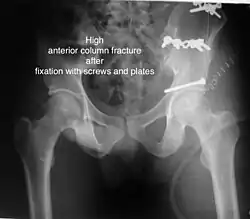

The final management depends on the size of the fragment(s), stability and congruence of the joint. In some cases traction for six to eight weeks may be the only treatment required; however, surgical fixation using screw(s) and plate(s) may be required if the injury is more complex. The latter treatment will be called for if bone fragments do not fall into place, or if they are found in the joint, or if the joint itself is unstable.

High anterior column fracture 3 D CT scan picture -

High anterior column fracture after fixation with screws and plates